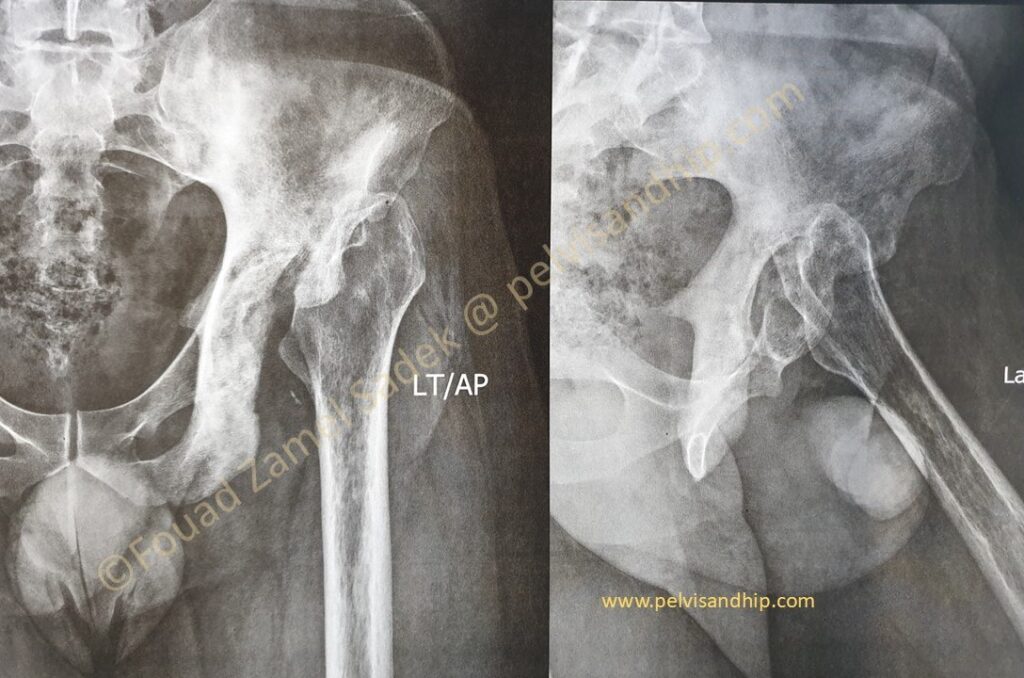

Axial CT cuts reveal a more extensive involvement of the hemipelvis with obvious skeletal changes in response to previous infection including a bony ankylosis of the left SI joint with some extension of the bone reaction in the ilium.

The dome level cuts of the acetabulum again confirms residual bone changes from the previous infection. This is also the best cuts to assess superior bone support and we can easily identify the superior defect at the level of the dome something that could very well require some form of reconstruction.